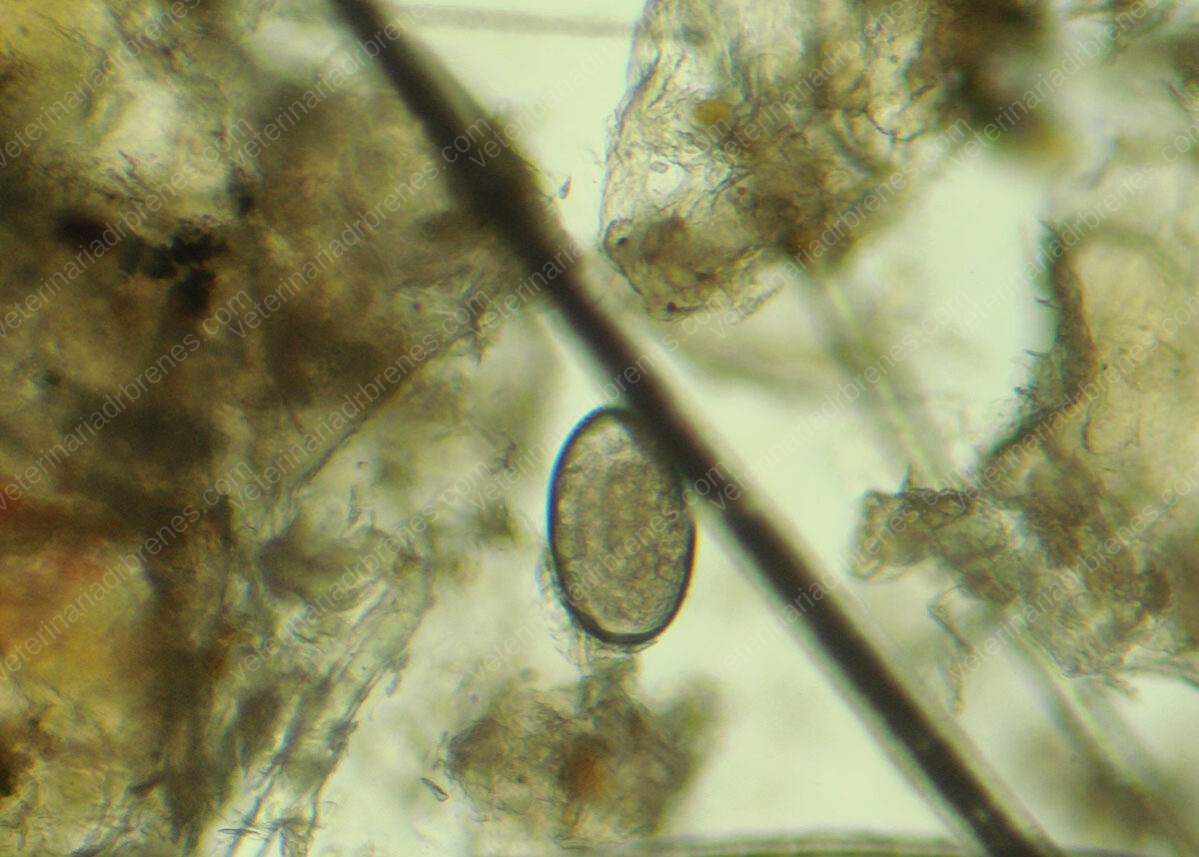

Las enfermedades de la piel en nuestras mascotas son muy comunes; pacientes con mucha picazón, piel reseca, lesiones en piel como las ronchas o pústulas, son motivos de consulta frecuente. Es por ello por lo que realizamos estudios como lo son los raspados de piel, para identificar la presencia o no de hongos, bacterias y ácaros; citologías de piel y biopsias en el caso de tumores y pruebas hormonales que nos ayuden a detectar pacientes con alteraciones de tipo endocrino que contribuyan a desórdenes en la piel como son los pacientes con hipotiroidismo.